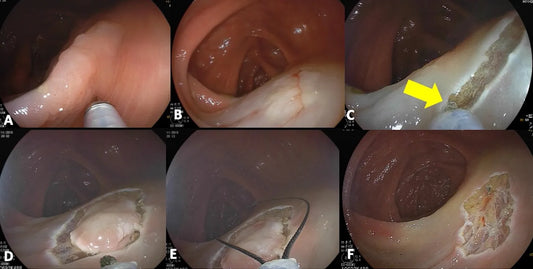

The Hybrid ESD-EMR Technique Explained

Discover the groundbreaking method that's transforming endoscopic resection for optimal lesion removal.